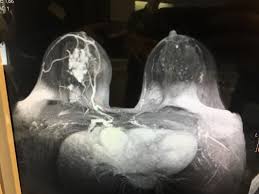

Learn more about cat scans today. What you need to know. Monitor the effectiveness of certain. The whole appointment can take up to an hour and a half depending on which part of your body they are scanning. The pet scanner detects signals that are given off from the tracer. Diagnose and assess breast tumors. Ct examination of the pancreas should always be done with maximum amount of contrast at a maximum flow rate, because both on a poor quality scan it is impossible to rule out emboli. Ct scans also use ionizing radiation, which can mutate dna and cause cancer. Doctors use a computed tomography (ct) scan, also called a cat scan, to find cancer. You can have a ct scan done at the radiology or radiation oncology center of a hospital. A ct scan can show whether breast cancer has spread to the lungs or liver. A radiographer operates the scanner. Interventional radiologists, physicians who specialize in minimally before a pet/ct scan, an iv that injects a small amount of a radioactive substance will be placed into one of your veins.

The lifetime risk from typical ct scan exposure is small for older adults sue to the long time it takes cancer to develop. Ct scans can detect bone and joint problems, like complex bone fractures and tumors. Also, during the examination, the diagnostician draws attention to the condition of the lymph nodes for the detection of metastases. Each has its own strengths. Ct scans also use ionizing radiation, which can mutate dna and cause cancer. How does a ct or cat scan work? Detection of cancer prior to onset of symptoms (via several tests/imaging). This provides a series of images from many different angles. If cancer was detected through the nhs breast screening programme, you may need another mammogram or ultrasound scan. Bone scans, positron emission tomography (pet), and computed tomography (ct) all continue to be employed alone or in combination for the detection of breast cancers suspected to have spread. What does a ct scan show? Your healthcare provider will order a ct scan to help make a diagnosis of references. The whole appointment can take up to an hour and a half depending on which part of your body they are scanning.

The proposed method is used to detect the cancerous cells. Breast cancer type and stage: If cancer was detected through the nhs breast screening programme, you may need another mammogram or ultrasound scan. These techniques include ct scans, mri scans and radioisotope scans. Staging and treatment of breast cancer. The whole appointment can take up to an hour and a half depending on which part of your body they are scanning. What does a ct scan show? And of the 70 million scans done last year — double the a heart scan, for example, increases the risk of lung or breast cancer, while a head scan raises since lung cancer is usually detected when it's already advanced, too late for it to be cured. Monitor the effectiveness of certain. Ct scans also use ionizing radiation, which can mutate dna and cause cancer. This lung cancer awareness month learn how future processing is able to detect lung cancer from ct scans with the help of ai. What does a ct scan show? The lung cancer detection is the extension of the image processing that produces the results of feature extraction and feature selection after segmentation.